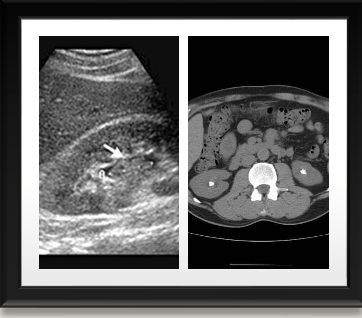

Invetsiagtions for ureteric stones

Ureteric stones

Obstructive Uropathy

PUJO- PELVI-URETERIC JUNCTIONAL OBSTRUCTION